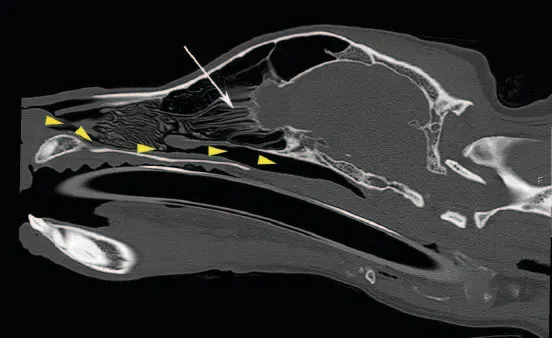

Sagittal CT image of the nasal cavity of a dog. Arrowheads illustrate the path the tube must take. The tube must pass over the incisive bone and roots of the incisors before it can be directed through the ventral meatus, ventral to the ventral nasal concha (arrow) and ethmoid turbinates.